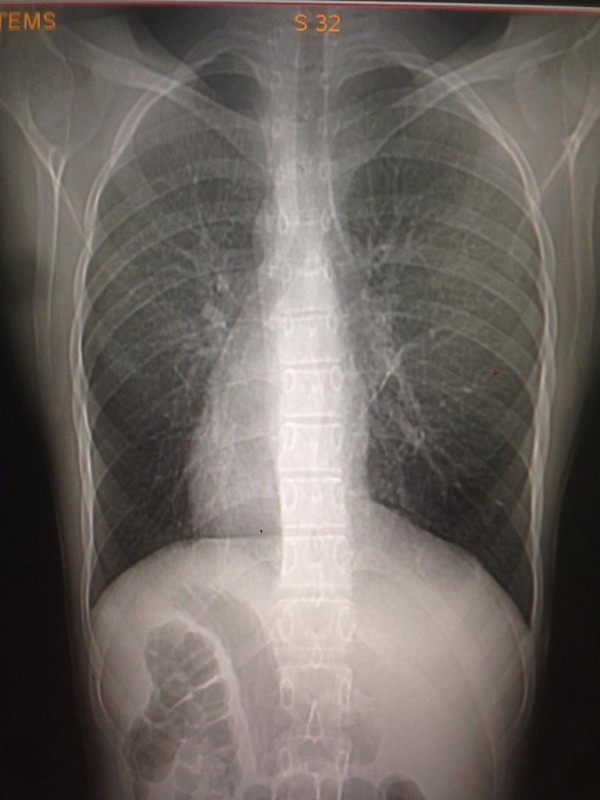

Транспозиция внутренних органов. Снимок предоставлен Сундетом Саргеловым

К сожалению, точных статистических данных обо всех казахстанцах, сердце которых расположено с правой стороны грудной клетки, нет. Однако, по словам медработника, в нашей стране ситуация аналогична мировой. Таким образом, если население Казахстана в среднем составляет 18 миллионов, то по вычету получается, что среди нас живет около 1800 правосердечников. В основном люди узнают об аномалии, когда делают рентген. К тому же зачастую посмертное вскрытие не проводят, так как родные умершего бывают против этой процедуры.